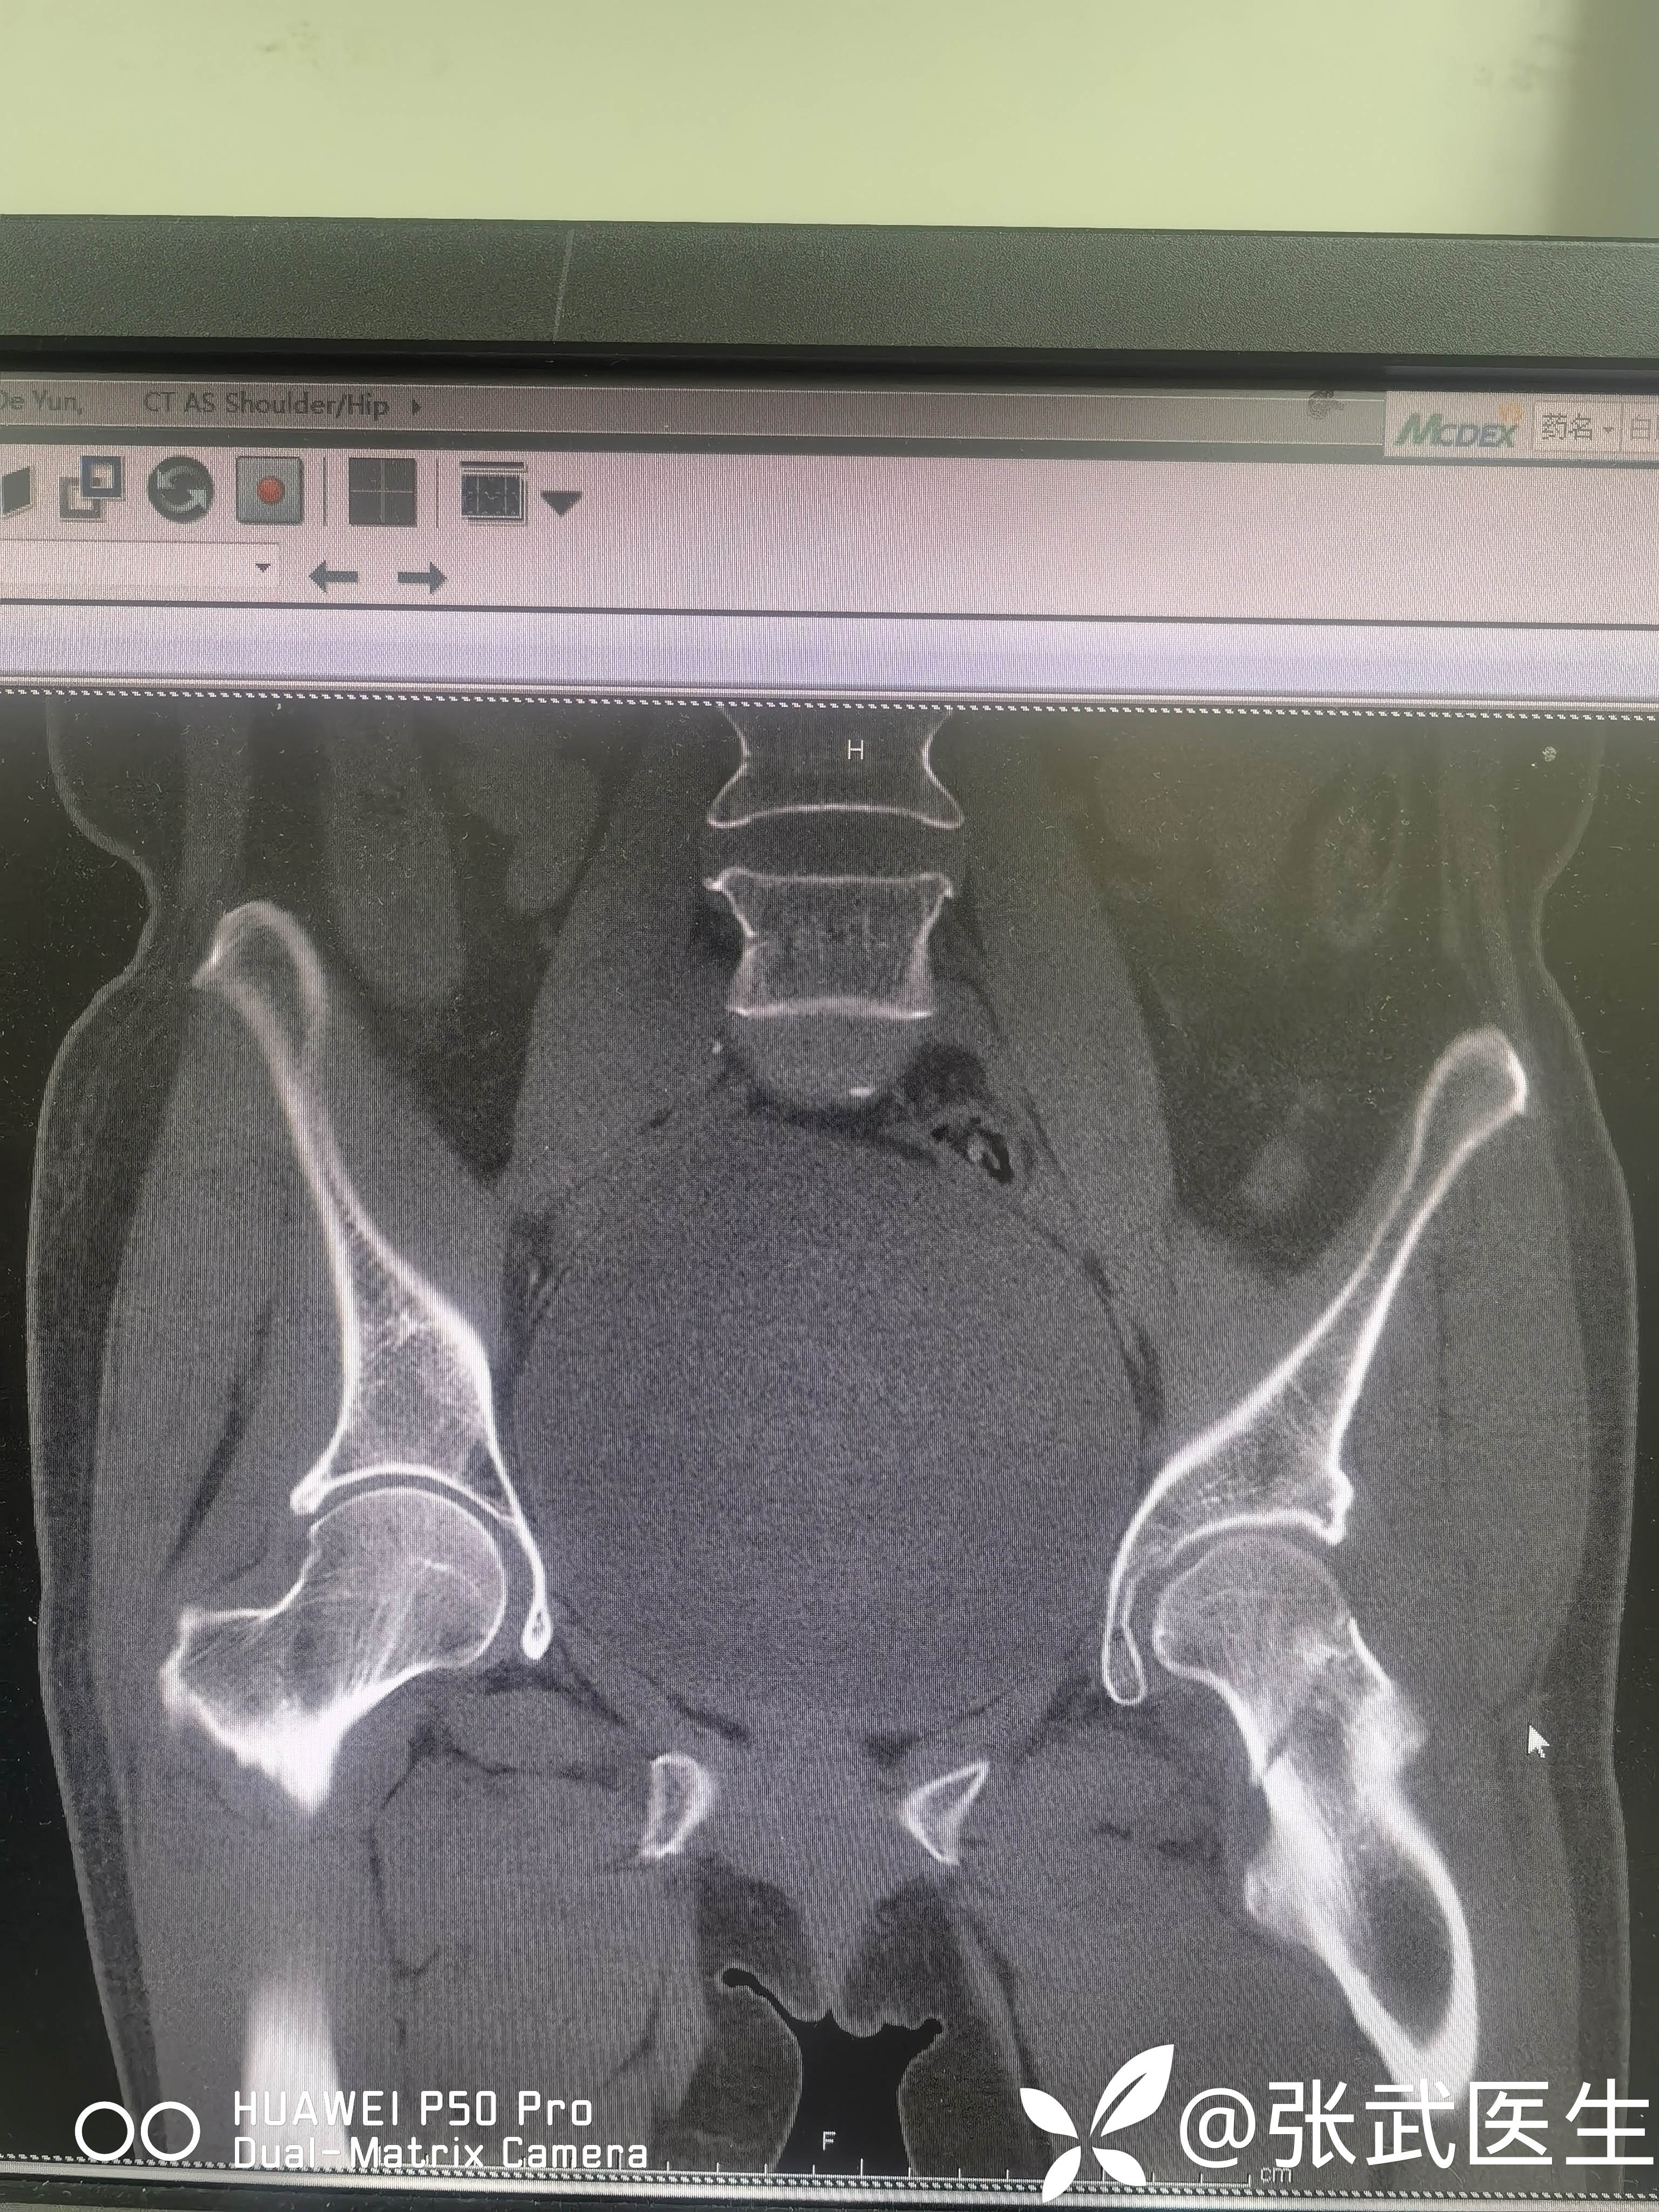

诊断:左股骨颈骨折 Garden II型

术前:

pauwels>50度